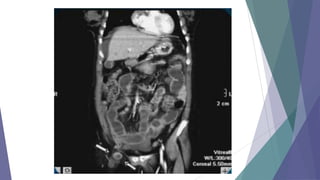

TAC para pacientes con dolor de abdomen con origen desconocido

INDICACIONES:

• Colecciones, abscesos, tumores.

• Estudio del retroperitoneo.

• Dudas diagnósticas con otros métodos

 TAC para pacientescon dolor de abdomen con origen desconocido INDICACIONES: • Colecciones, abscesos, tumores. • Estudio del retroperitoneo. • Dudas diagnósticas con otros métodos